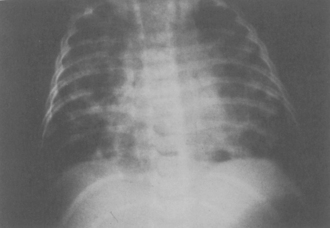

Chest radiograph changes may worsen over the first 72   hours following aspiration, and then begin to clear (Fig. 9-17). Abnormalities can persist for 4 to 6 weeks, lagging far behind clinical improvement. Marked perihilar densities are initially visible, followed by progression to consolidation. Air trapping with the possible formation of pneumatoceles and cysts may occur rarely. Infiltrates are most likely to be observed in the right upper lobe of the supine, intubated patient, but they may be present in any lobe. The presence of a normal chest radiograph, normal breath sounds, and lack of pulmonary symptoms does not rule out the possibility of aspiration pneumonia.

image

Fig. 9-17 Aspiration pneumonia. A, This child aspirated during intubation and so was supine during the aspiration episode. Bilateral infiltrates are present, particularly to the right lung and to the left upper lobe. B, This child ingested kerosene and then vomited and aspirated the hydrocarbon. Diffuse bilateral infiltrates are present, consistent with permeability pulmonary edema and early acute respiratory distress syndrome. The endotracheal tube is readily identifiable (arrow).

(Chest radiographs courtesy Sharon Stein and Dennis Stokes, Vanderbilt University Medical Center, Nashville, TN.)